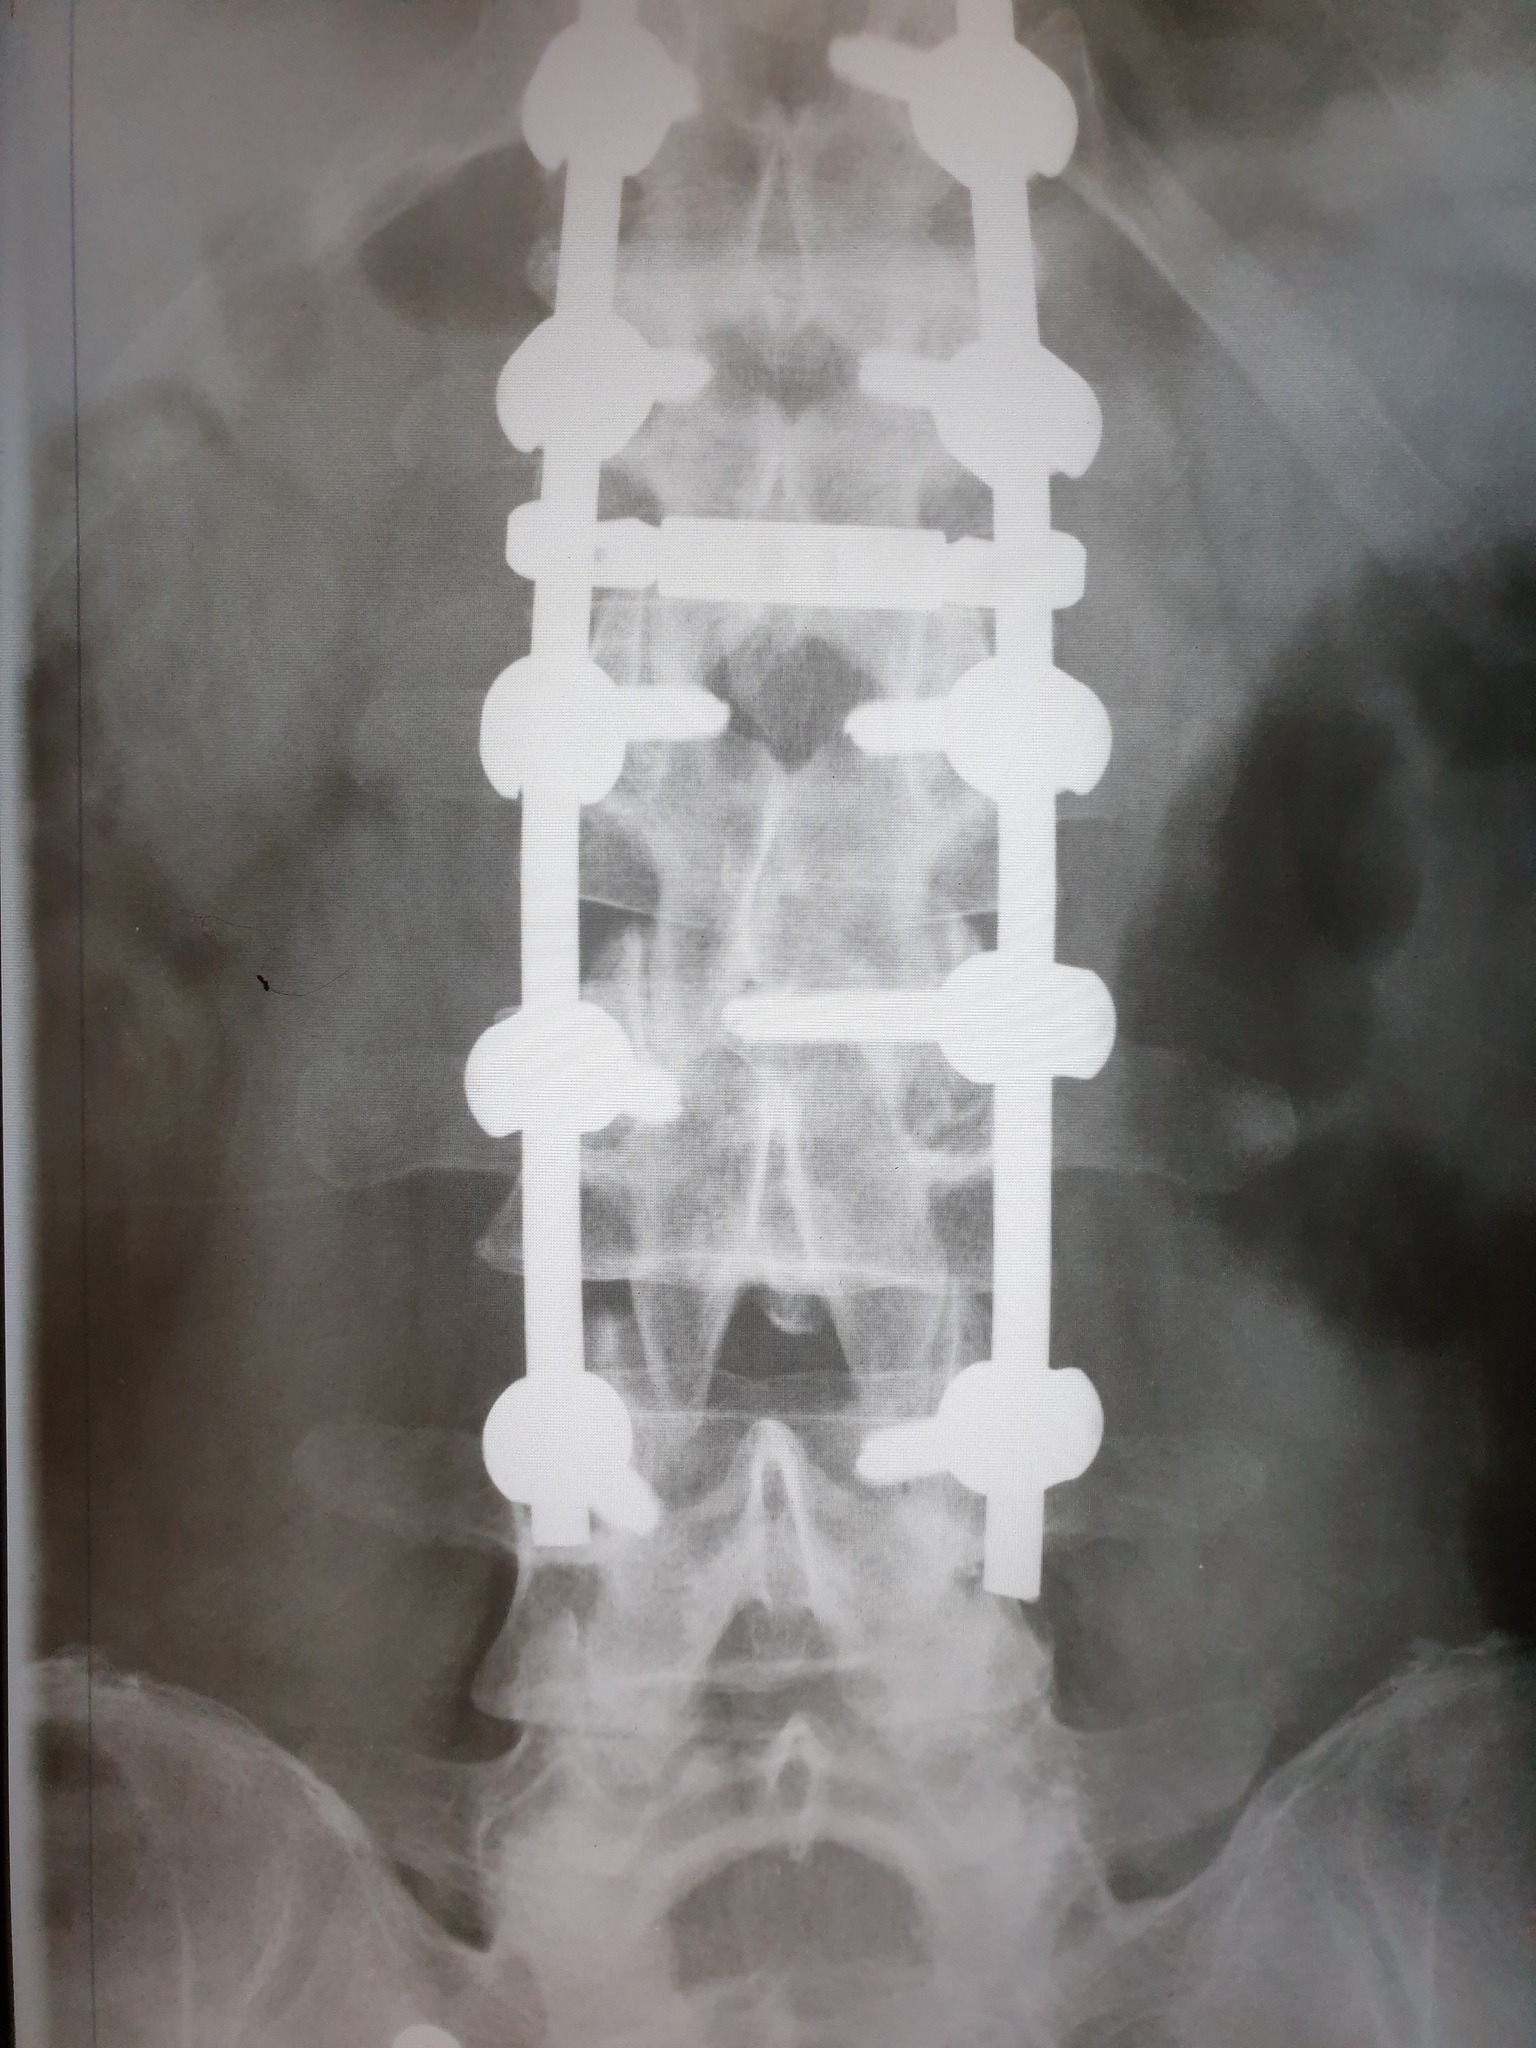

Nakon što je 11. februara doživio povredu na radnom mjestu, tačnije nakon što je pao sa lotri i slomio kičmu na dva mjesta Nino Katić je odlučio da progovori i sa svima podijeli svoje iskustvo, ali i pokaže zastrašujuće povrede koje je zadobio.

– Šta dobiješ u “Centrumu” kada zbog njihovog neispravnog sredstva za rad slomiš kičmu na dva mjesta i ostaneš invalid? Pa kod neljudi dobiješ otkaz, i to poštom – rekao je Katić, a zatim je opisao šta je dovelo do teške nesreće koja se dogodila 11. februara, ali i svemu što je slijedilo nakon tog dana.

– Došao je i 11. februar, taj crni 11. kada sam pao sa lotri, samo pukoše ispod mene i završio sam sa dvostrukim lomom kičme. Inspekciju nisu zvali, jedva je i Hitna pozvana, a kažu prva riječ šefova je bila: “Jeste li morali zvati Hitnu?”, Nakon toga me je zamjenica porodične doktorke oštetila svojim neradom jer mi nije htjela na vrijeme izdati uputnicu za ljekarsku komisiju na koju sam zbog toga zakasnio dva dana i uslijed čega mi je ljekarska komisija promjenila status iz “povreda na radu: DA” u “povreda na radu: NE”, znači svjesno se lagalo na zvaničnom dokumentu – objasnio je Katić za Srpskainfo.